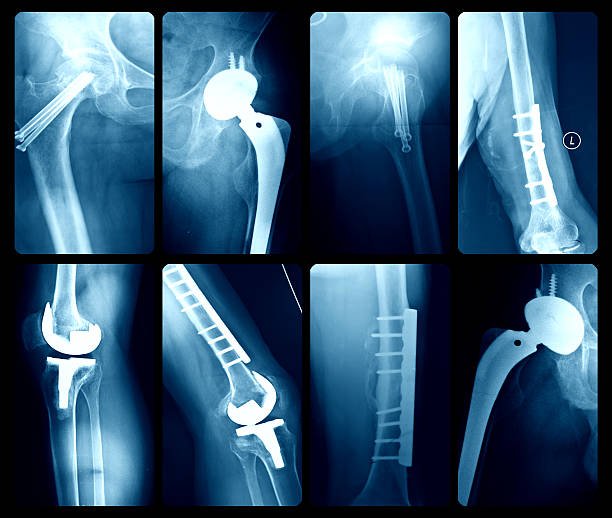

Arthroscopic management of joint problems and sports related injuries have excellent outcomes and early return to pretrauma functions because of minimally invasive nature of these surgeries.

At our hospital, arthroscopy and sports medicine are key areas of focus, offering minimally invasive solutions for joint issues and sports-related injuries. These advanced procedures allow for precise diagnosis and treatment with minimal tissue disruption, leading to faster healing and reduced postoperative discomfort.

Knee , shoulder, hip and ankle arthroscopic procedures are performed at our institution.

Common arthroscopic procedures performed include